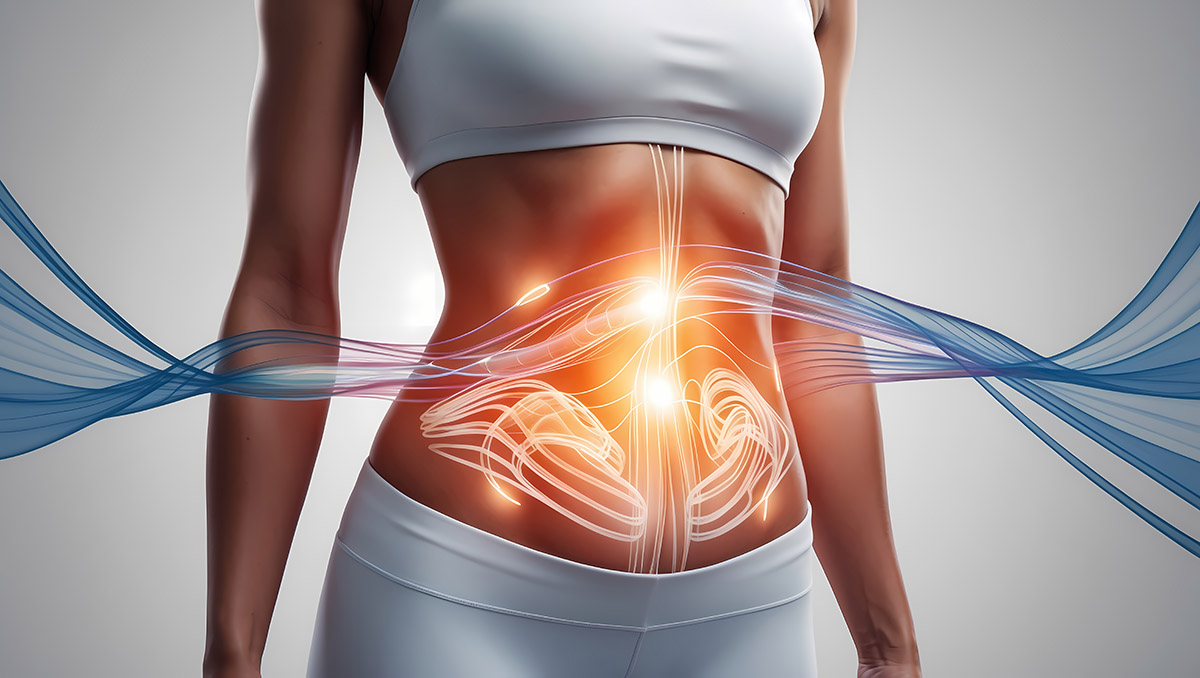

Probiotika und Sporternährung: Leistungssteigerung durch Darmgesundheit

Die Verbindung zwischen Darmgesundheit und sportlicher Leistung

Darmreinigung und Detox: Mythen und Fakten

Der Trend zur "inneren Reinigung"

Darmgesundheit und Allergien: Der versteckte Zusammenhang

Die steigende Prävalenz von Allergien

Probiotika-Supplementierung: Wann, wie und welche?

Die wachsende Bedeutung von Probiotika

Probiotika und Gewichtsmanagement: Der Darm als Schlüssel

Die unterschätzte Rolle des Darmmikrobioms beim Körpergewicht